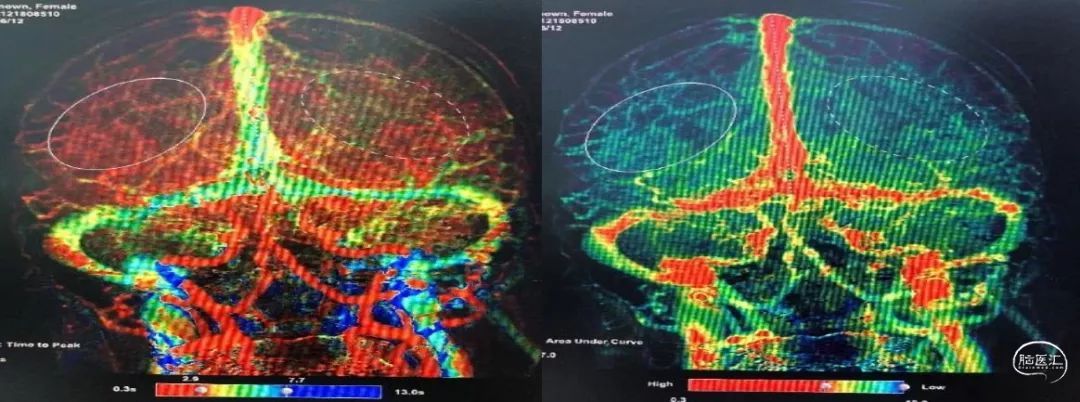

没有颅内出血,急诊复查造影,左侧颈动脉支架内通畅,左侧前循环颅内动脉显影良好,再次除外急性脑梗死,给与静脉乌拉地尔控制血压、甘露醇脱水降颅压治疗后,患者病情稍有缓解,NIHSS 12分,同时查灌注成像(图5)、TCCD(图6)未提示术后高灌注表现。

图5:DSA下行脑灌注检查(到达时间、达峰时间)双侧无明显差异

其次,高灌注综合征?造影显示颈动脉仅为中度狭窄,术后高灌注可能性应该很低,并且高灌注综合征往往发生在术后3小时之后,而该患者出现在支架释放后的第5分钟。XPER-CT未见颅内出血, CT上提示的左侧半球造影剂外渗伴皮层水肿,是造影剂脑病?

过度灌注综合征?这个词是我最不喜欢的![]() ,总认为这就是一个CAS术后出血的垃圾桶,很多人喜欢将术后出血全都归咎于CHS,这个病人可是做了灌注,都是正常的呀;

所以,就个人的判断而言,我更倾向于陈飞医生所说的“祸不单行”,也就是在梗塞急性期血脑屏障破坏基础上的造影剂正常“过度”灌注,可能有点绕啊![]() 。具体而言,虽然血流是正常的,但梗塞后早期的BBB破坏,导致局部相对 “过度”的容易被造影剂影响,尤其是高渗造影剂,从而造成特殊的造影剂脑病,但还是仅限于猜测。